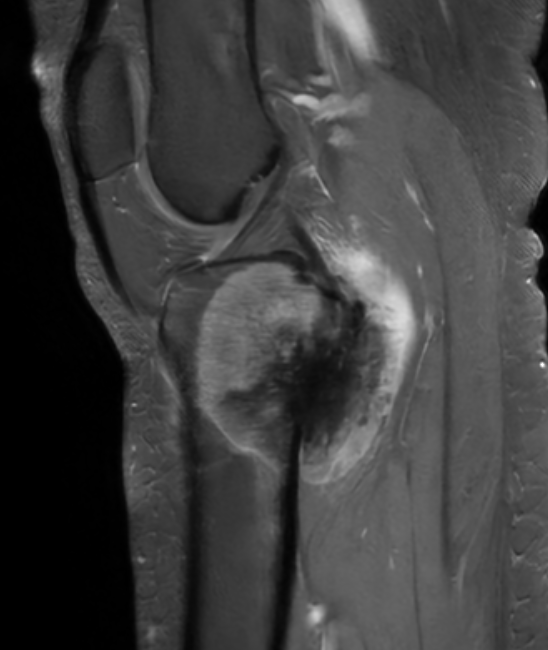

MRI

Parosteal osteosarcoma posterior distal femur

Parosteal osteosarcoma anterior tibia

Parosteal osteosarcoma posterior tibia

Pathology

Gross

Attached to cortex

Does not penetrate medullary cavity